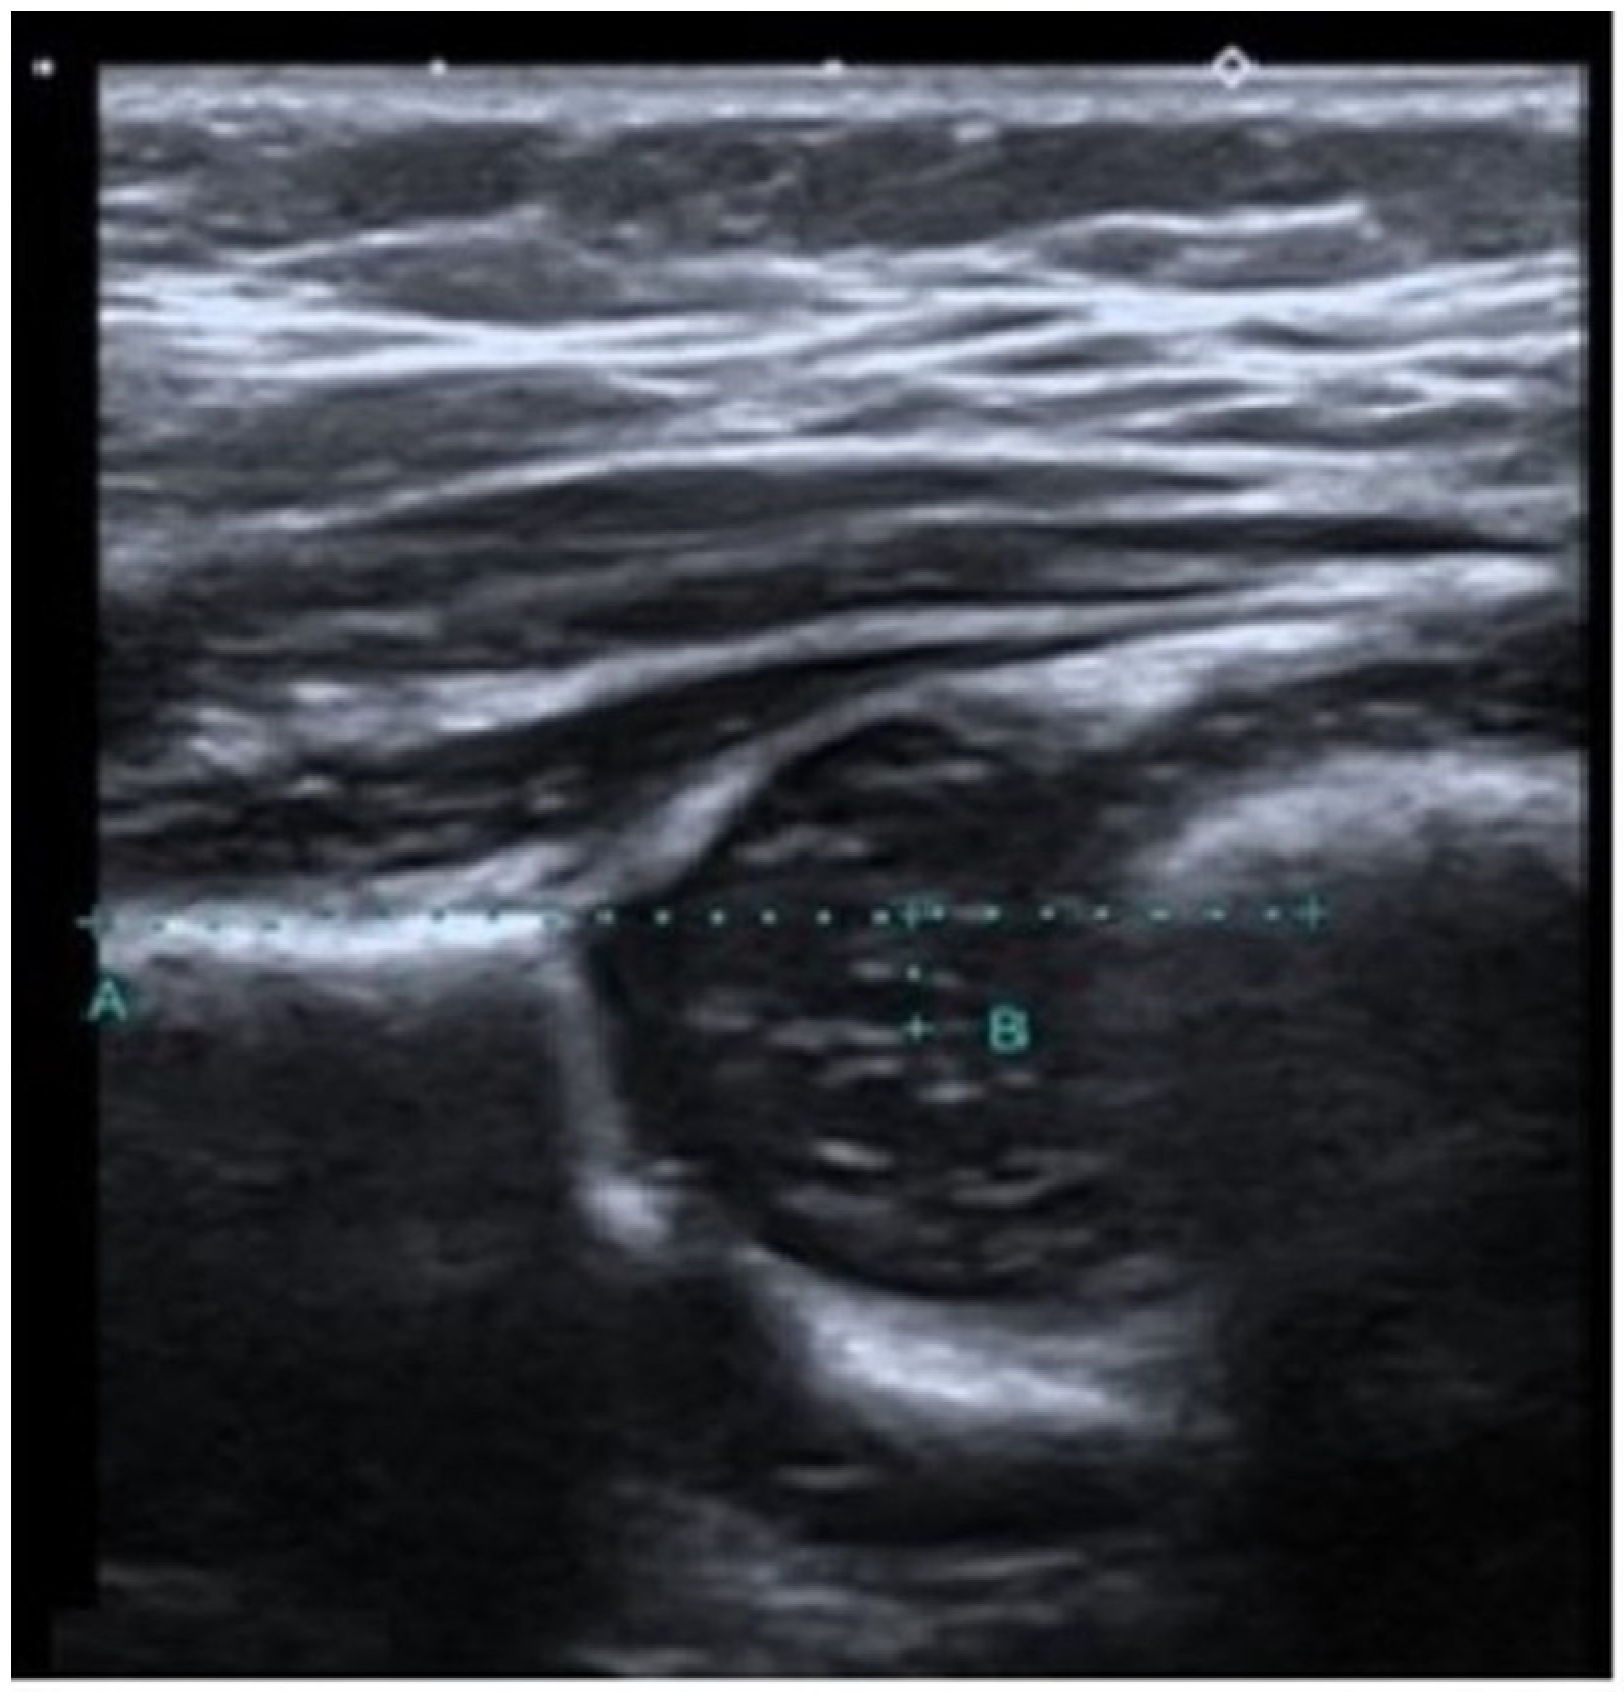

The recently devised technique involved measuring the distance between the central femoral head and a horizontal line that passes through the iliac wing. This measurement is referred to as the FMD value (Figure 1). The determination of the center of the femoral head in hip US pictures was achieved by calculating the average of the longest vertical diameter of the femoral head, as measured in the coronal plane (Figure 2).

Figure 1. The iliac bone (single arrow), iliac roof (double arrow), and femoral head (arrow head) demonstrated in picture form. The distance indicated by the star is the measurement between the femoral decapitation center and the horizontal line passing through the iliac bone.